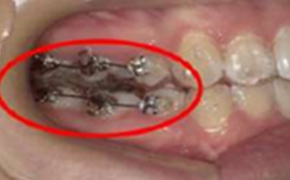

マウスピース矯正中

マウスピース矯正中に、マウスピースだけでは動きにくい場合は、ゴムの力を借りて歯を動かす場合があります。

また、部分的にワイヤーを使用する場合があります。

フック&ゴム

上下いずれかのマウスピースにあるフックと、歯の表面につけるリンガルボタンという金属の突起に、顎間ゴムというゴムをひっかけて、噛み合わせを整えます。マウスピース装着時間と同等の時間使用する必要があります。